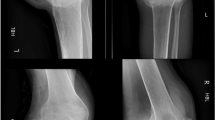

External skeletal fixation for the treatment of femoral shaft fractures in the spinal cord injury patient is simple to apply, provides good fracture immobilization, affords easy access to the limb for skin care, and permits significant patient mobility and early return to pre-fracture functional status. This paper presents the rationale for the use of, and the technique of application of, the Wagner leg lengthening device for the external skeletal fixation of femoral shaft fractures in the SCI patient.

Baird, R., Kreitenberg, A. Treatment of femoral shaft fractures in the spinal cord injury patient using the wagner leg lengthening device. Spinal Cord 22, 366–372 (1984). https://doi.org/10.1038/sc.1984.59